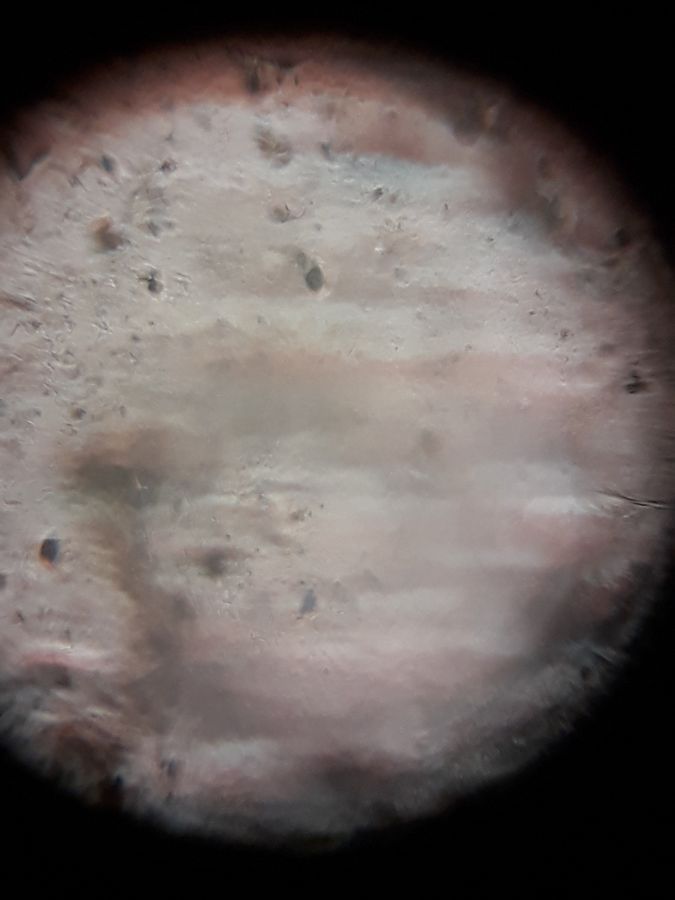

ཕྲ་སྲིན།

140x Magnification